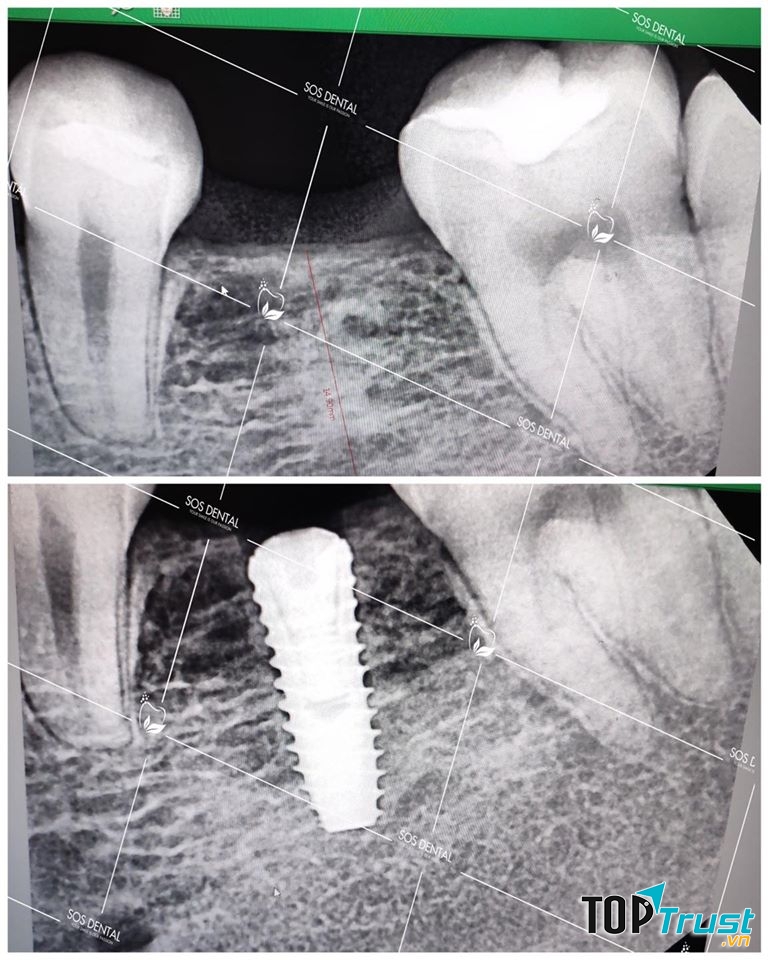

Nha Khoa Quốc Tế SOS Dental

Trồng răng Implant là giải pháp phục hình răng bị mất nhanh chóng, hiệu quả, được nhiều chuyên gia đánh giá cao vì phương pháp này giúp khôi phục thẩm mỹ, cải thiện chức năng ăn nhai, độ bền cao có khả năng duy trì bền vững đến trọn đời cho răng. Nha Khoa Quốc Tế SOS Dental thực hiện Công nghệ từ Hàn Quốc - Mỹ - Đức và các kỹ thuật: